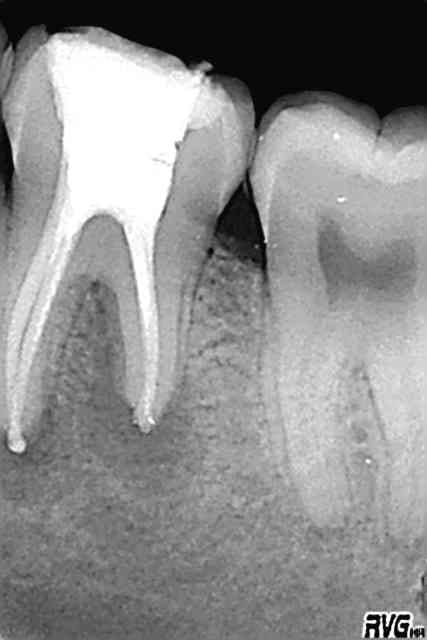

Allez j'en mets une autre, satisfaisante en densité

edit : tant que ya pas un mac spadden pété on est pas sur que c'est bien tassé :p

Non je rigole mais c'est l'instrument que je casse le plus, avec les limes K pour le cathétérisme. Jamais de protaper.

ça me pose pas de problème de le laisser noyé dans la gutta.

Mcspadden3 bkutva - Eugenol

Mcspadden1 hsrtpy - Eugenol

Mcspadden2 bj8onp - Eugenol